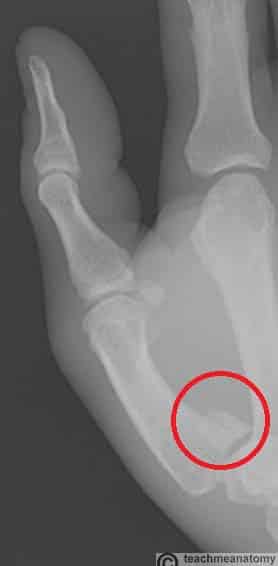

The bones of the hand provide support and movement to the soft tissues. They can be categorised into three different types: Carpal bones (proximal) – a set of eight irregularly shaped bones. They are located in the area of the wrist. Metacarpals – a set of five bones, each one related to a digit. They are located in the area of the palm. Phalanges (distal) – the bones of the digits. The thumb has two phalanges, whilst the rest of the fingers have three. In this article, we shall look at the anatomy of the bones of the hand – their structure, articulations and clinical correlations. By TeachMeSeries Ltd (2025) Fig 1Overview of the bones of the hand. Pro Feature - 3D Model You've Discovered a Pro Feature Access our 3D Model Library Explore, cut, dissect, annotate and manipulate our 3D models to visualise anatomy in a dynamic, interactive way. Learn More Carpal Bones The carpal bones are a group of eight irregularly shaped bones. They are organised into two rows – proximal and distal: Proximal row: Scaphoid Lunate Triquetrum Pisiform (a sesamoid bone, formed within the tendon of the flexor carpi ulnaris) Distal row: Trapezium Trapezoid Capitate Hamate (has a projection on its palmar surface, known as the ‘hook of hamate’ In the proximal row, the scaphoid and lunate articulate with the radius to form the wrist joint (radiocarpal joint). The distal row of carpal bones articulate with the metacarpals at the carpometacarpal joints. The carpal bones collectively form an arch in the coronal plane. A membranous band, the flexor retinaculum, spans between the medial and lateral edges of the arch, forming the carpal tunnel. Structures pass through the carpal tunnel to enter and exit the volar (anterior) aspect of the hand. By TeachMeSeries Ltd (2025) Fig 2Palmar view of the carpal bones of the left hand. By TeachMeSeries Ltd (2025) Fig 3Transverse section of the carpal tunnel. Clinical Relevance Scaphoid Fracture The scaphoid bone of the hand is the most commonly fractured carpal bone – typically by falling on an outstretched hand (FOOSH). In a fracture of the scaphoid, the characteristic clinical feature is pain and tenderness in the anatomical snuffbox. The scaphoid is at particular risk of avascular necrosis after fracture because of its so-called ‘retrograde blood supply’ which enters at its distal end. This means that a fracture to the middle (or ‘waist’) of the scaphoid may interrupt the blood supply to the proximal part of the scaphoid bone rendering it avascular. Patients with a missed scaphoid fracture are likely to develop osteoarthritis of the wrist in later life. By Gilo1969 (Own work) [CC-BY-SA-3.0], via Wikimedia Commons Fig 4Radiograph of a scaphoid fracture. Adapted from work by Iiibalesiii [CC BY-SA 4.0] Fig 5The blood supply to the scaphoid bone runs from distal to proximal. Metacarpal Bones The metacarpal bones articulate proximally with the carpals, and distally with the proximal phalanges. They are numbered, and each is associated with a digit: Metacarpal I – thumb. Metacarpal II – index finger. Metacarpal III – middle finger. Metacarpal IV – ring finger. Metacarpal V – little finger. Each metacarpal consists of a base, shaft and a head. The medial and lateral surfaces of the metacarpals are concave, allowing attachment of the interossei muscles. Clinical Relevance Fractures of the Metacarpals The metacarpal bones are common sites of injury. Two common fracture patterns include: Boxer’s fracture – A fracture of the 5th metacarpal neck. It is usually caused by a clenched fist striking a hard object. The distal part of the fracture can become angulated, producing shortening of the affected finger. Bennett’s fracture – A fracture of the 1st metacarpal base, caused by forced hyperabduction of the thumb. This fracture extends into the first carpometacarpal joint leading to instability and subluxation of the joint. As a result, it often needs surgical repair. By TeachMeSeries Ltd (2025) Fig 6Bennett’s fracture. Phalanges The phalanges are the bones of the fingers. Each phalanx consists of a base, a shaft and a head. The thumb has a proximal and distal phalanx, while the rest of the digits have proximal, middle and distal phalanges. Do you think you’re ready? Take the quiz below Pro Feature - Quiz The Bones of the Hand: Carpals, Metacarpals and Phalanges Question 1 of 3 Submitting... Skip Next Rate question: You scored 0% Skipped: 0/3 1800 More Questions Available Upgrade to TeachMeAnatomy Pro Challenge yourself with over 1800 multiple-choice questions to reinforce learning Learn More Rate This Article